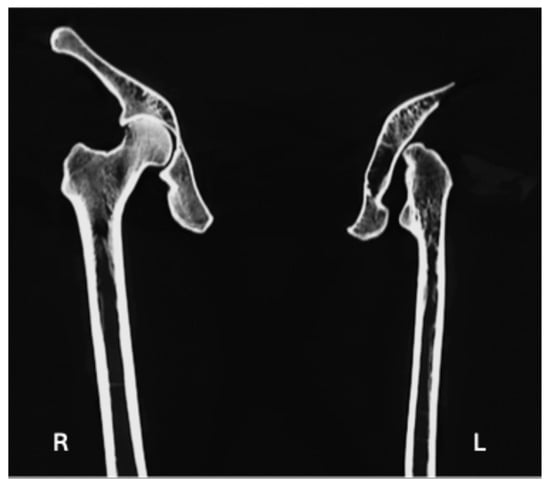

| Hypoplastic/aplastic femoral head (Figure 2b) | X | X |

| Lack of development of the intertrochanteric crest (Figure 2a and Figure 4) | X | X |

| Lack of development of the trochanteric fossa (Figure 2a and Figure 4) | X | X |

| Uppermost origin area for Vastus Lateralis as a flat spike (Figure 2a) | X |

| Triangular: the base facing the obturator foramen and the apex was directed postero-superiorly | Type 1 [32]: smooth shallow depression as articular surface developed just around the AIIS area, which was shifted laterally | Head: hypoplastic/aplastic | Subchondral sclerosis occurring at the knee joint margins |

| Change in the posterodistal area, leading to the shifting of the spine of ischium antero-laterally | Trochanteric fossa not developed | ||

| Flat groove for the Obturator Externus | Intertrochanteric crest not fully developed | ||

| Wide acetabular notch | Uppermost attachment area for Vastus Lateralis as a flat spike | ||

| Inverted limbus | Shortening of the bone | ||